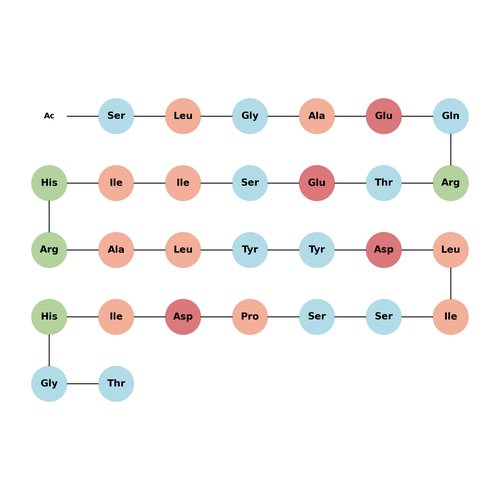

Fórmula:C144H227N41O47

Sinónimos:- L-Threoninamide, N-acetyl-L-seryl-L-leucylglycyl-L-alanyl-L-α-glutamyl-L-glutaminyl-L-arginyl-L-threonyl-L-α-glutamyl-L-seryl-L-isoleucyl-L-isoleucyl-L-histidyl-L-arginyl-L-alanyl-L-leucyl-L-tyrosyl-L-tyrosyl-L-α-aspartyl-L-leucyl-L-isoleucyl-L-seryl-L-seryl-L-prolyl-L-α-aspartyl-L-isoleucyl-L-histidylglycyl-

CAS:Fulipiftide is a short peptide derived from pigment epithelium-derived factor (PEDF). It stimulates the amplification of nuclear stem cell factor+TSPC by activating the ERK2 and STAT3 signaling pathways. Fulipiftide also exhibits anti-inflammatory properties and is applicable in research on acute tendon injuries.Fórmula:C144H227N41O47Forma y color:SolidPeso molecular:3284.59